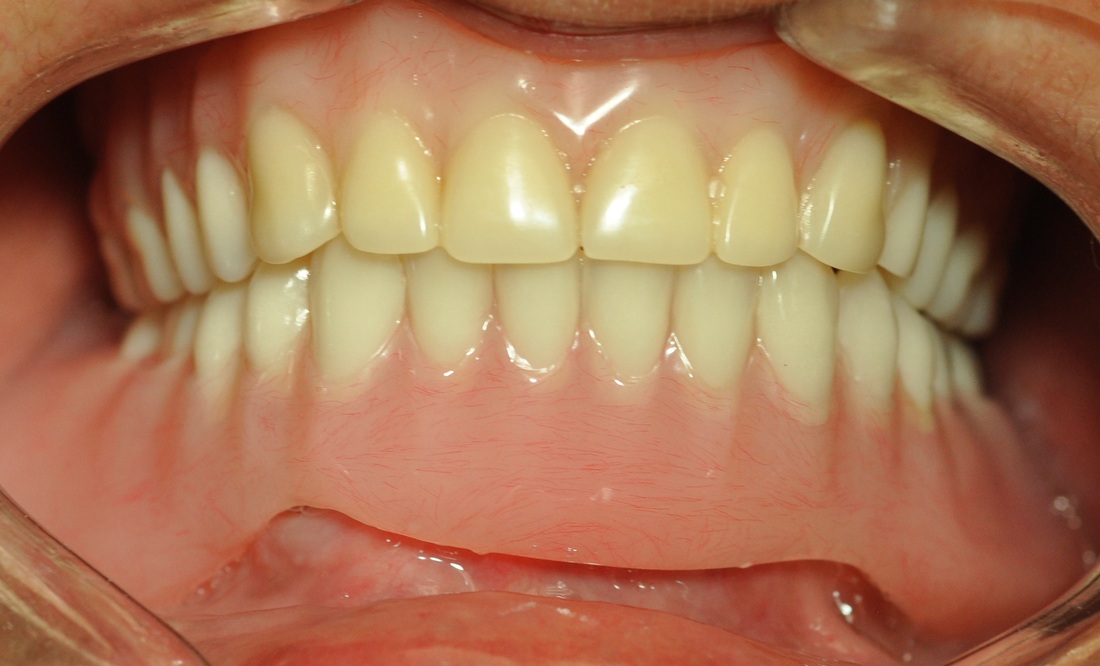

COMPREHENSIVE DENTAL REHABILITATION

A patient presented with partial teeth loss, periodontal disease, vertical bite collapse, wear on remaining teeth and smile issues.

The patient also suffered from frequent headaches, sore neck muscles, pain and clicking in both TMJs. After thorough and comprehensive evaluation- including neuromuscular diagnostic workup- a new physiological bite was established.

Missing teeth were replaced with dental implants. Teeth, damaged by bruxism (clenching and grinding), were restored with new myobite using all-ceramic veneers and crowns. During his 3-year follow-up visit the patient reported no headaches and no pain in the TMJs, improved sleep and dramatically decreased soreness of the neck muscles.